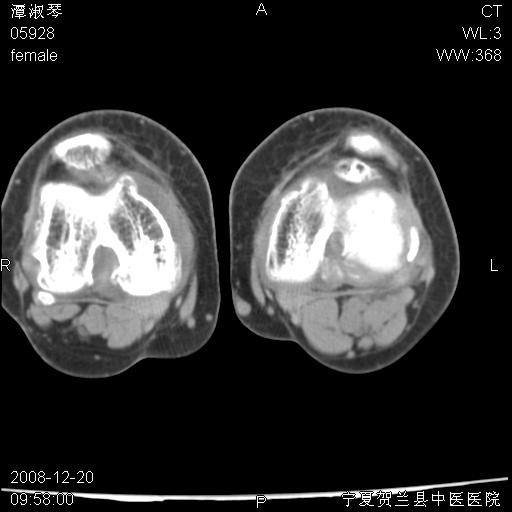

标题: CT17526:请各位看看是啥? [打印本页]

标题: CT17526:请各位看看是啥?

支持骨梗死,退行性骨关节病,膝关节积液.

考虑骨梗死可能性大

骨梗死可能性大

左股骨下段骨梗死。双膝退变。

左胫骨下端松质骨及髓腔内可见点片状高密度灶,骨皮质无明显膨胀及变薄。病变范围较长。支持骨梗死,退行性骨关节病,膝关节积液